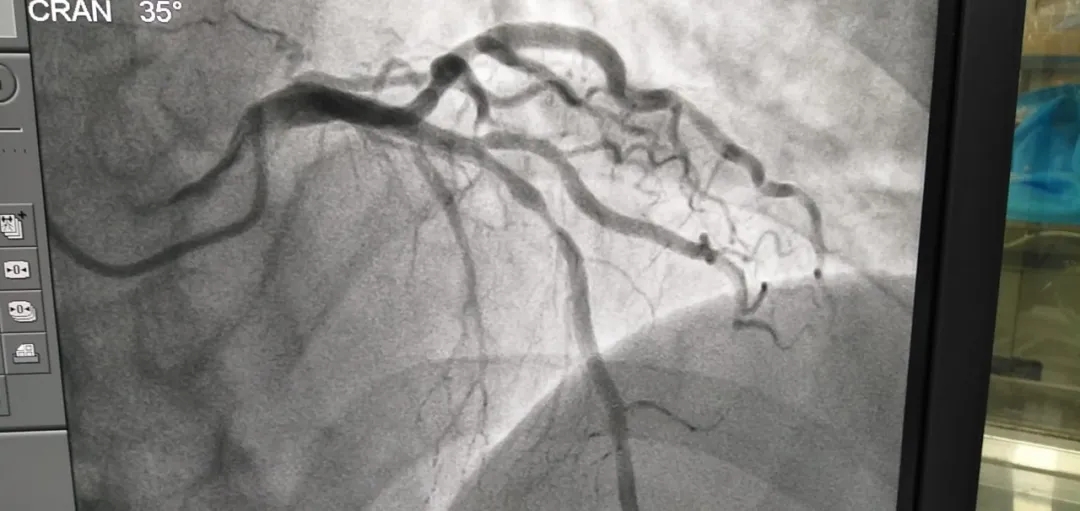

冠脉介入手术中需要密切观察有创血压、压力波形、心电波形、心率、氧饱和度等各项指标,因此除了少不了优秀的介入术者外,更需要熟练操作各项手术设备的技术工程师。手术过程均比较顺利,其中一名患者冠状动脉粥样硬化性情况复杂,经过对患者的病情详细地分析研究并精心做好术前各项准备后,专家在数字减影血管造影机(DSA)导引下,在为患者施行局部麻醉后,顺利进行了冠状动脉造影术+支架植入术。

(冠脉手术进行中)